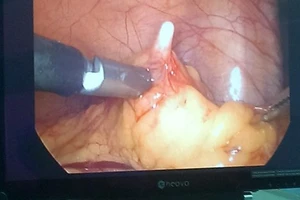

Phẫu thuật lấy vòng tránh thai lạc vào ổ bụng

Mổ nội soi lấy vòng tránh thai lạc vào ổ bụng